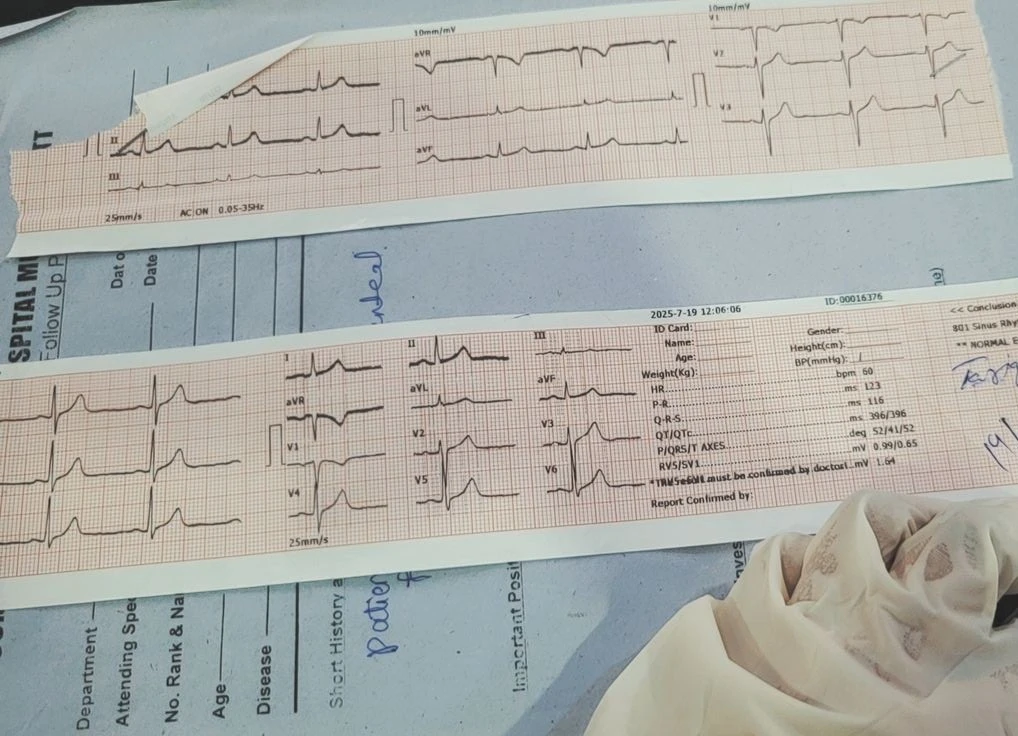

datorită protocoalelor stricte de siguranță, echipament medical portabil de ultimă generație (ecograf wireless 305mm, EKG holter,

obstetrică, tiroidă), EKG și monitorizare cardiacă Holter, terapii IV personalizate cu vitamine (Glutațion, Magneziu, Vitamina C),